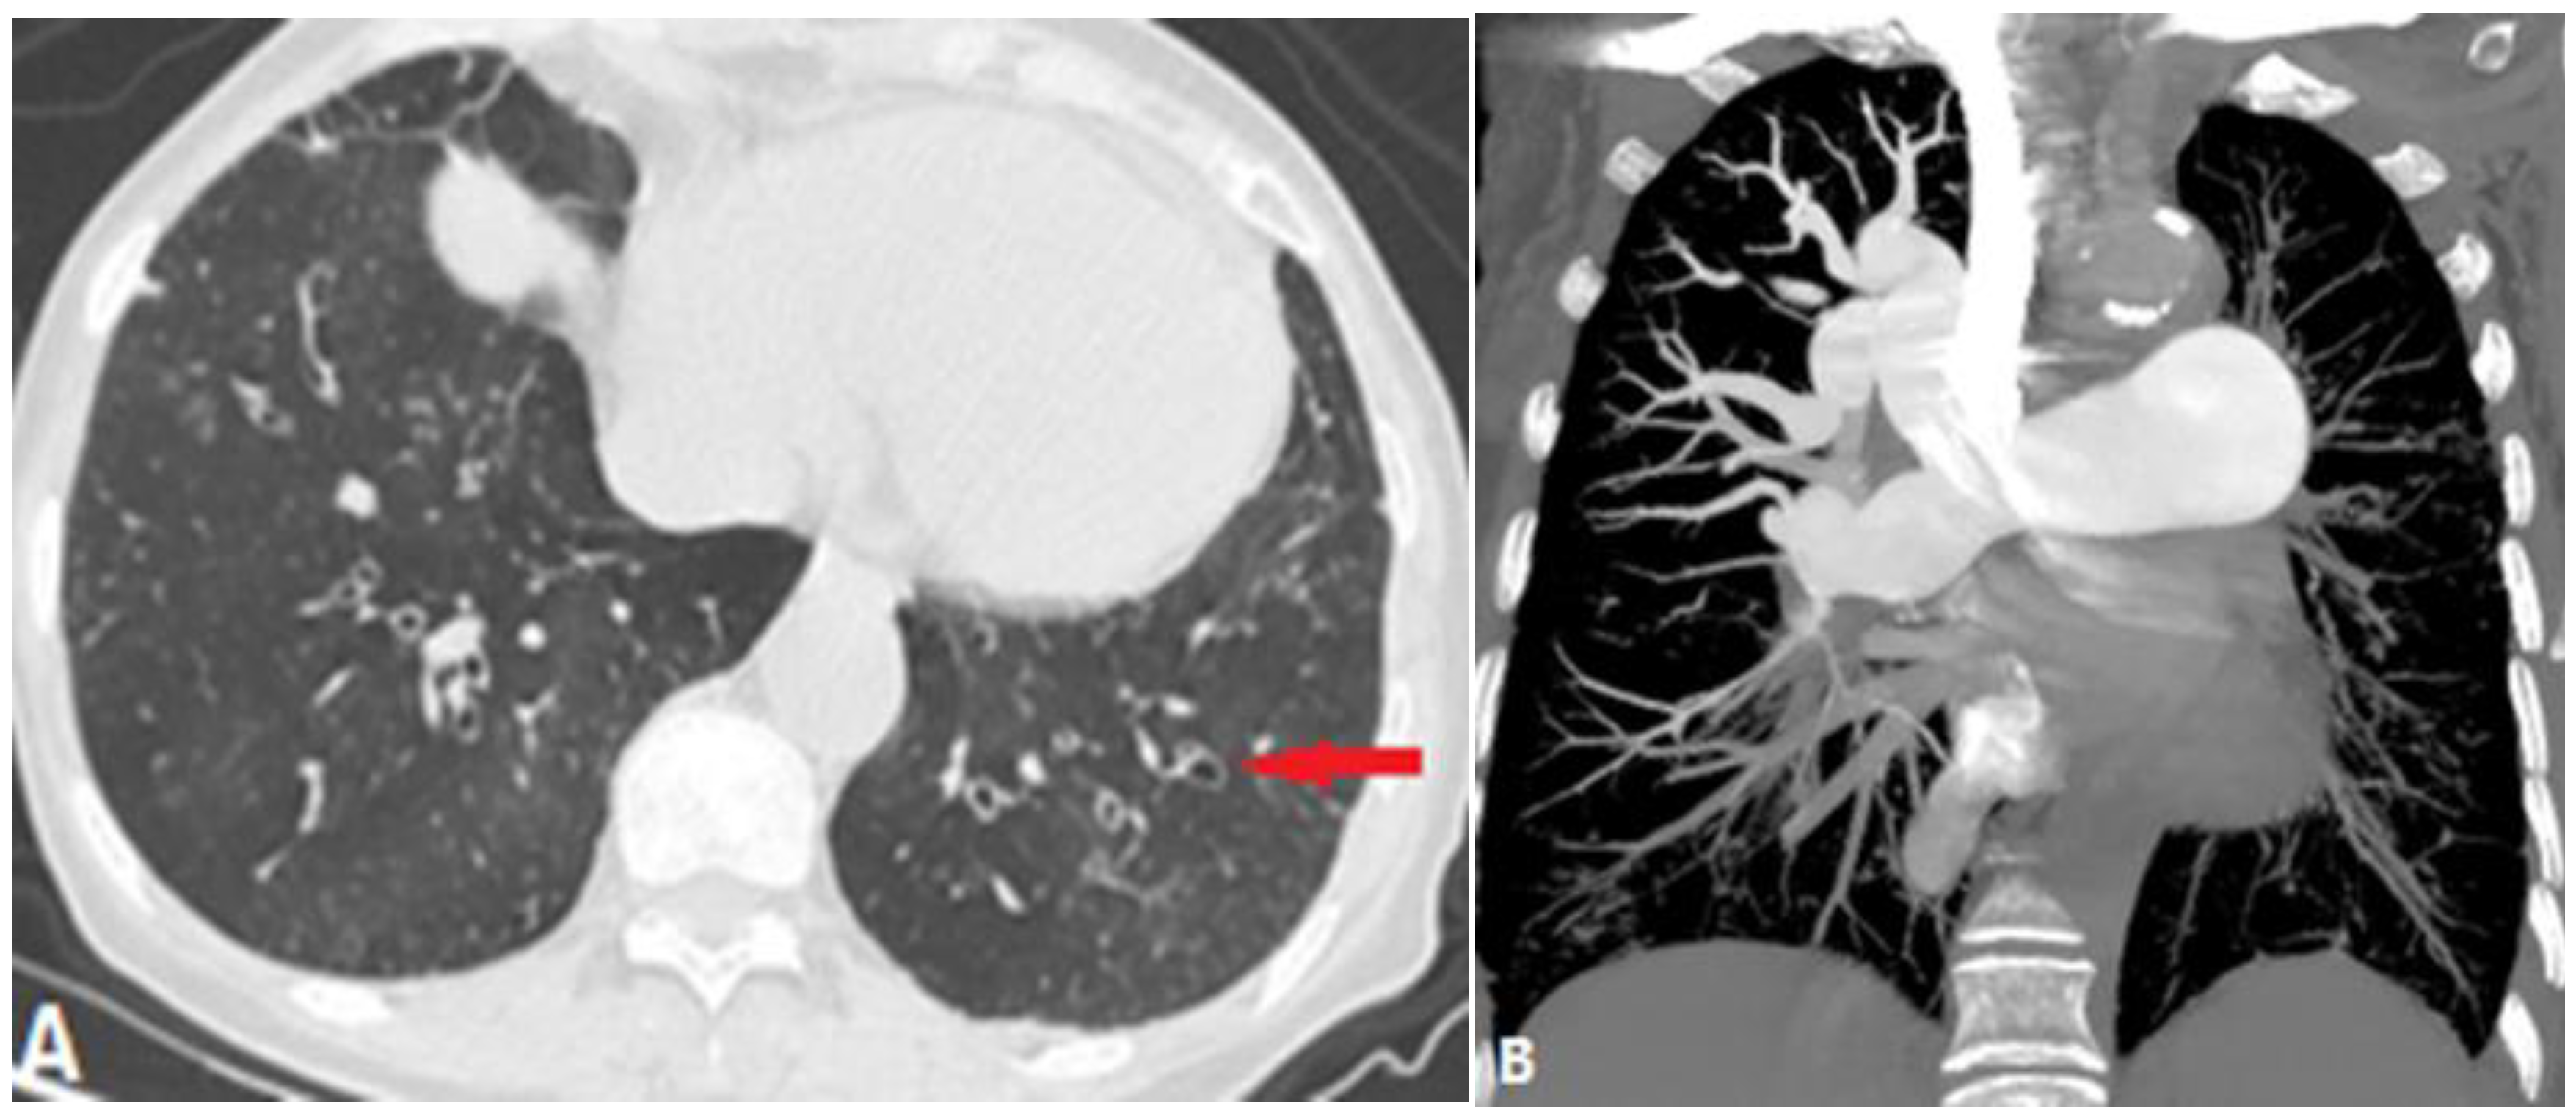

5. Complications of Radiofrequency Ablation of Atrial Fibrillation

- Alfudhili, K.M.; Hassan, H.H.; Abdullah, H.; Sherbiny, M. Pulmonary vein occlusion and lung infarction complicating non-treated moderate single pulmonary vein stenosis after radiofrequency ablation of atrial fibrillation. BJR Case Rep. 2017, 18, 20160091. [Google Scholar] [CrossRef]

- Xu, L.; Cui, L.; Hou, J.; Wang, J.; Chen, B.; Xue, X.; Yang, Y.; Wu, J.; Chen, J. Clinical characteristics of patients with atrial fibrillation suffering from pulmonary vein stenosis after radiofrequency ablation. J. Int. Med. Res. 2020, 48, 0300060519881555. [Google Scholar] [CrossRef]

- Ravenel, J.G.; McAdams, H.P. Pulmonary venous infarction after radiofrequency ablation for atrial fibrillation. AJR Am. J. Roentgenol. 2002, 178, 664–666. [Google Scholar] [CrossRef]